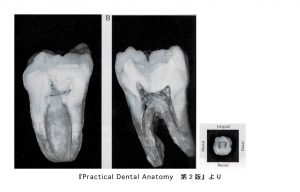

実際の下顎大臼歯の中身

これは下顎大臼歯を歯の神経に達するまでの穴をあけて真っ二つに割ったものです。根の先端にいくほどカーブしているのがわかりますね。